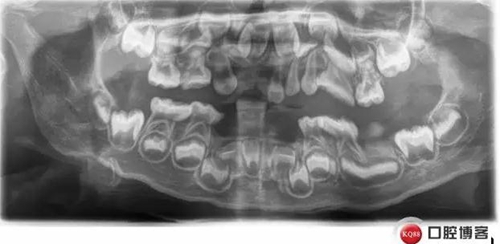

復(fù)診X線:

低磷脂酶癥是一種罕見的遺傳代謝異常,缺乏組織非特異性堿性磷酸酶活性,口腔表現(xiàn):牙齒萌出遲緩,乳恒牙均易早失,脫落牙齒的牙根長度無變化。乳前牙最易受累而早失。病程中無明顯疼痛,牙周無明顯炎癥。X線片示牙釉質(zhì)正常,髓腔和和根管增大,牙槽骨有吸收。